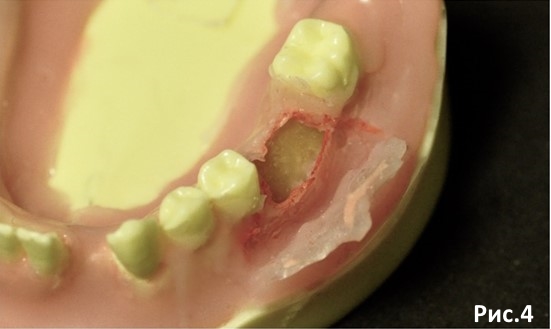

Далее распатором отслаиваем надкостницу в апикальном направлении формируя поднадкостничный карман на глубину длинны планируемых имплантатов. Рис.4